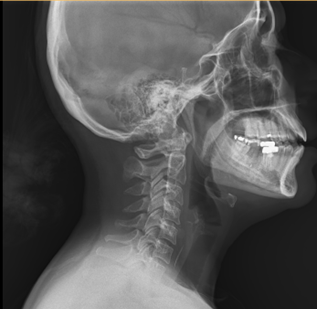

A rapid X-ray confirmed the presence of a fish bone lodged in the upper esophagus—a potentially dangerous situation if not addressed quickly.